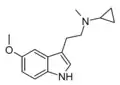

| McPT | artificial | H | CH3 | C3H5 | N-Methyl-N-cyclopropyltryptamine | 1373918-63-8 |